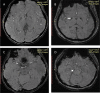

Individuals with Rett syndrome (RTT) commonly demonstrate Parkinsonian features and dystonia at teen age; however, the pathological reason remains unclear. Abnormal iron accumulation in deep gray matter were reported in some Parkinsonian-related disorders. In this study, we investigated the iron accumulation in deep gray matter of RTT and its correlation with dystonia severity. We recruited 18 RTT-diagnosed participants with MECP2 mutations, from age 4 to 28, and 28 age-gender matched controls and investigated the iron accumulation by susceptibility weighted image (SWI) in substantia nigra (SN), globus pallidus (GP), putamen, caudate nucleus, and thalamus. Pearson's correlation was applied for the relation between iron accumulation and dystonia severity. In RTT, the severity of dystonia scales showed significant increase in subjects older than 10 years, and the contrast ratios of SWI also showed significant differences in putamen, caudate nucleus and the average values of SN, putamen, and GP between RTT and controls. The age demonstrated moderate to high negative correlations with contrast ratios. The dystonia scales were correlated with the average contrast ratio of SN, putamen and GP, indicating iron accumulation in dopaminergic system and related grey matter. As the first SWI study for RTT individuals, we found increased iron deposition in dopaminergic system and related grey matter, which may partly explain the gradually increased dystonia.